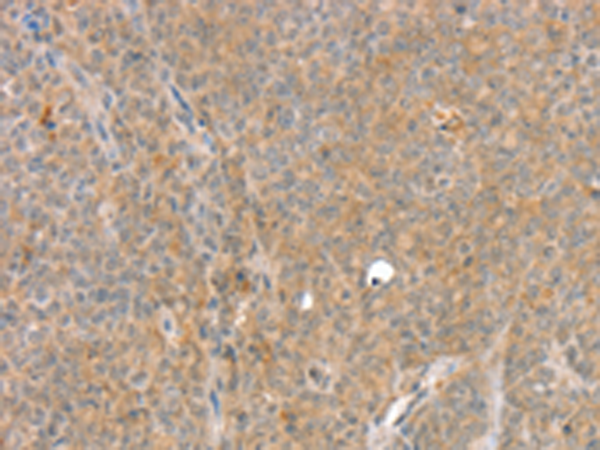

分类: 科研抗体货号: P12152别名: SSP3; Ulp1; SMT3IP1应用: IHC反应种属: Human, Mouse